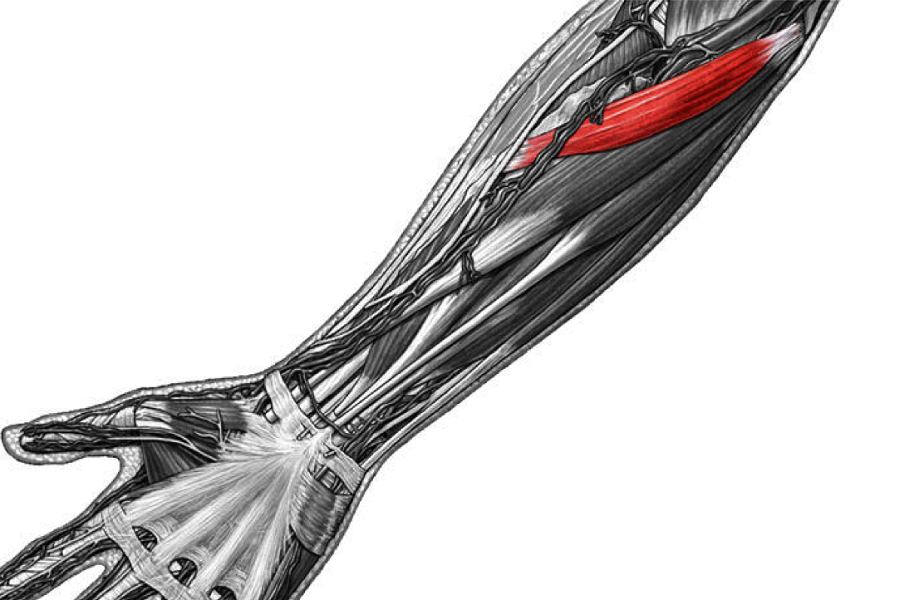

Анатомия мышцы Palmaris Longus